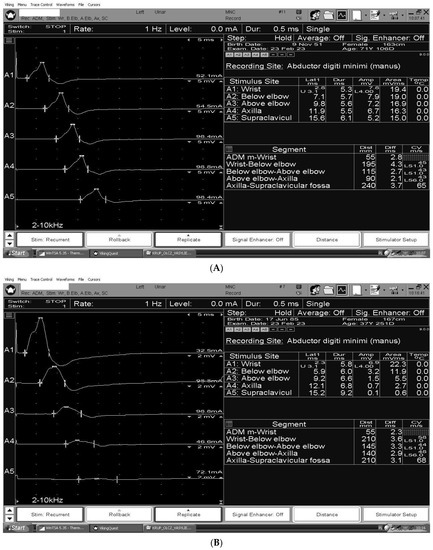

The figures summarize the characteristic nerve conduction study findings for CIDP [Figure 2A], GBS [Figure 2B] and MMN [Figure 2C] in the ulnar motor study, recording abductor digiti minimi, stimulating wrist (A1), below groove (A2), above groove (A3), axilla (A4), and Erb’s point (A5).

Figure 2.

(A) Ulnar motor study in a patient with CIDP. Gradual, slight reduction in CMAPs amplitude between stimulation points at the wrist and Erb’s point. According to motor nerve conduction criteria the 2021 EFNS/PNS consensus guidelines for CIDP motor conduction block or slowing is not considered in the ulnar nerve across the elbow. (B) Multifocal conduction blocks in the ulnar nerve in the patient with GBS. (C) Temporal dispersion in the ulnar nerve at the Erb’s point stimulation in the patient with MMN.